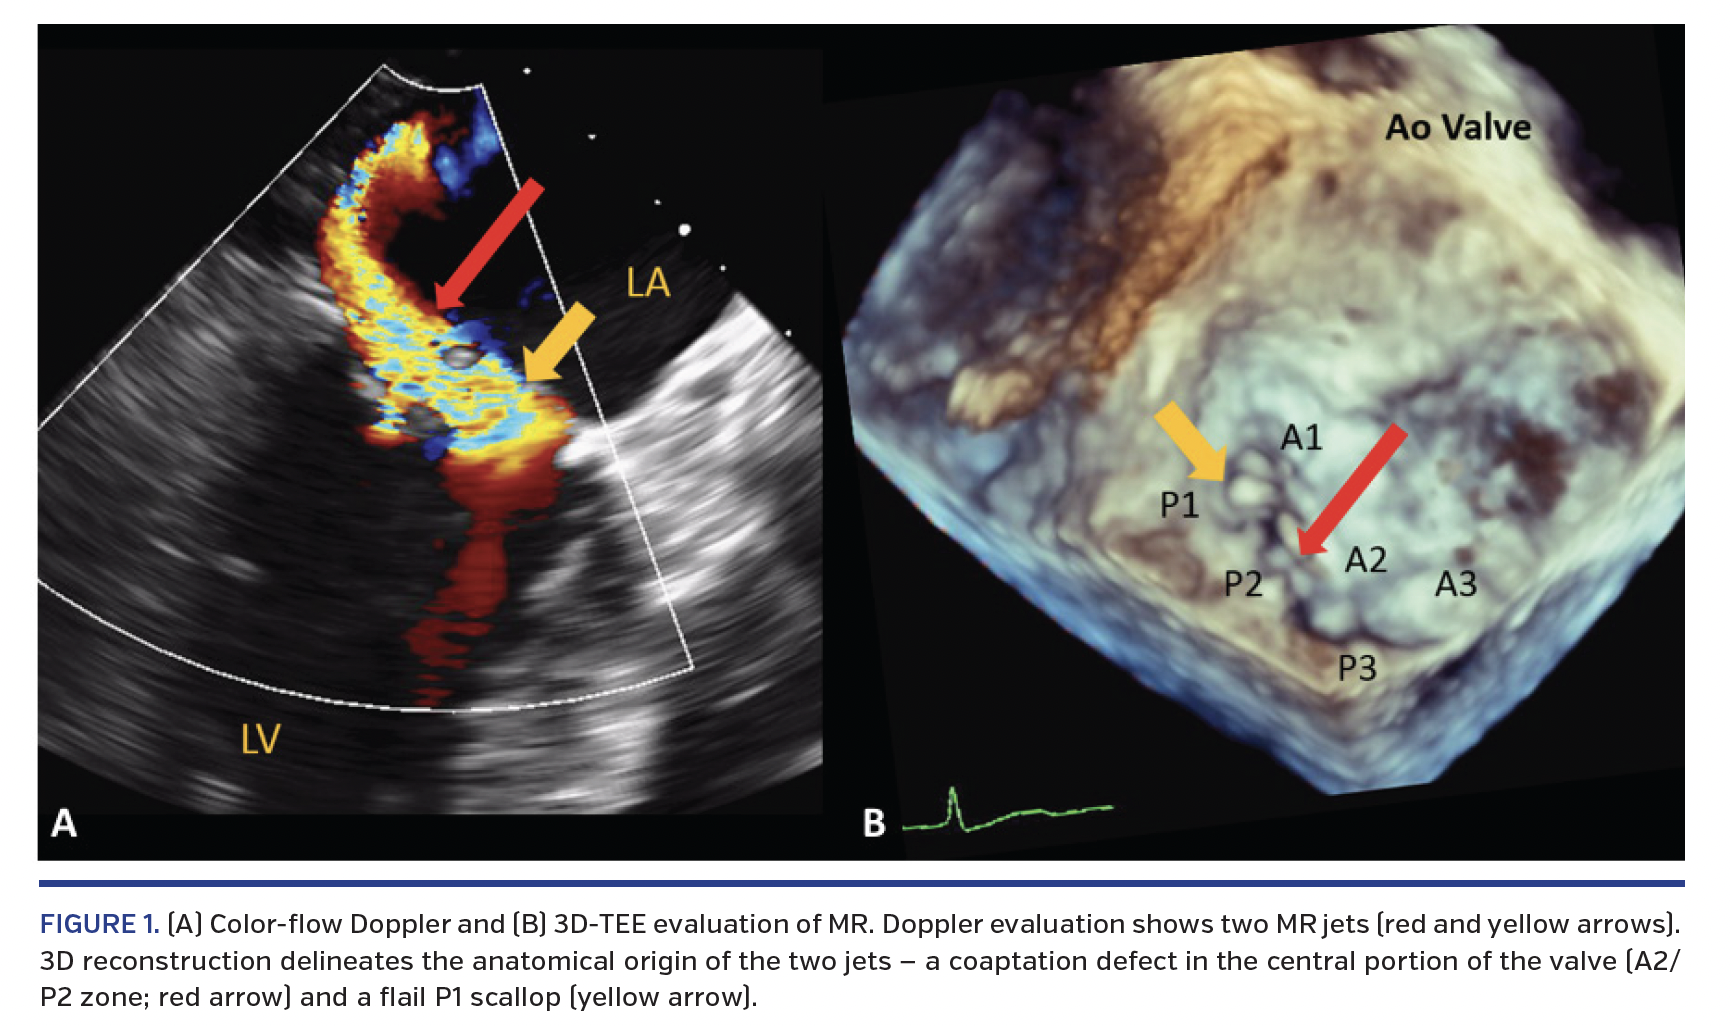

A 70-year-old woman was re-admitted to the emergency department with recalcitrant heart failure symptoms that had initially abated following initiation and optimization of diuretic therapy. Past medical history was significant for heart failure with preserved ejection fraction, chronic obstructive pulmonary disease, and aortic stenosis treated with transcatheter aortic valve replacement (TAVR) 3 years prior, with a 23 mm Edwards Sapien XT valve (Edwards Lifesciences). Physical exam was remarkable for bibasilar crackles, 3/6 pansystolic murmur heard best at the apex with radiation to the axilla, and 3/6 harsh, diastolic decrescendo murmur heard best at the lower left sternal border. Transthoracic echocardiogram showed severe mitral regurgitation (MR) with an eccentric posterolateral jet and moderate aortic regurgitation (AR) with peak velocity of 3.8 m/sec, mean gradient of 32 mm Hg, and valve area of 1.2 cm2. Three-dimensional transesophageal echocardiogram (3D-TEE) demonstrated two MR jets (Figure 1) and severe AR. There was a migrated aortic prosthesis below the native aortic valve leaflets (Figure 2). In addition, the displaced prosthesis may have disrupted the mitral subvalvular apparatus, leading to a flail P1 scallop. These findings were confirmed by inversion mode volume-rendered and multiplanar gated computed tomographic (CT) reconstruction (Figure 2E; Videos 1 and 2). A valve-in-valve TAVR was planned. Intraprocedural cone-beam CT imaging and aortic root angiogram showed the “slipped” Sapien XT valve (in comparison with the aortic root angiogram from 3 years ago) with severe AR, respectively (Figure 3). There was complete resolution of severe AR following valve-in-valve TAVR with a 23 mm Edwards Sapien 3 valve (Figure 4; Videos 3-5).